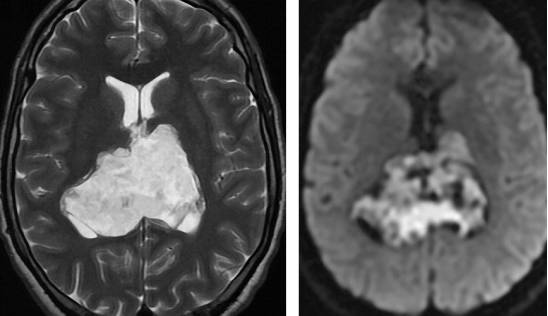

图11. 表皮样囊肿在T2加权相上与脑脊液呈等信号。弥散加权成像有助于鉴别蛛网膜囊肿,由于弥散受限和T2相上的透过性,表皮样囊肿在DWI上表现为高信号。